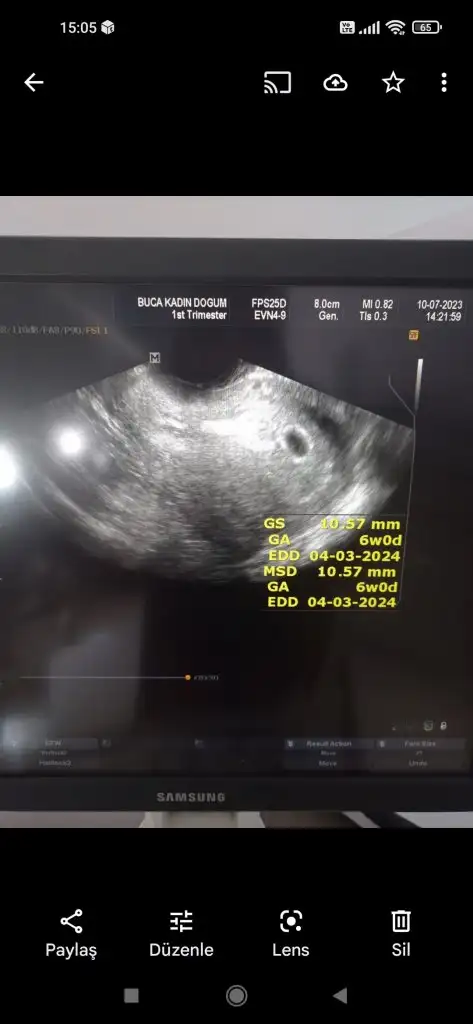

Merhaba banada tahmin yaparmisiniz.ultrason kağıdında 6+0 Altan muayne oldum .yorumlarsanız sevinirim.ama ben kese içinde iki yuvarlak görüyorum.